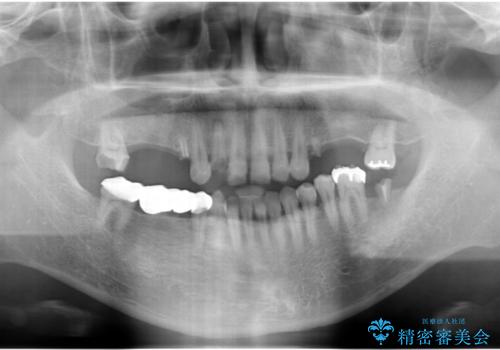

インプラント治療・セラミック治療を含む 全顎的虫歯治療

- 「 仕事が忙しく、虫歯を放置しすぎてしまった。この際全てきっちりと治したい。」と来院されました。

・歯の欠損

・虫歯

・深い虫歯

・欠損の放置による対合歯の挺出

・咬合平面の乱れ

・感染根管

以上のような問題を、徹底的な虫歯治療、歯周外科、インプラント治療、部分矯正治療、精密根管治療を用いてひとつずつ解決ししっかりと長期的に食事を楽しめるような口腔内環境の再構築を目指します。